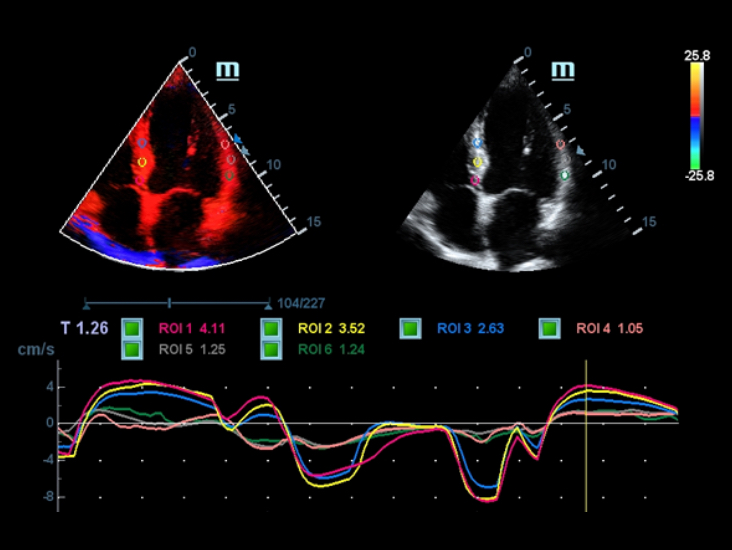

DC-40 ―¹ Full HD –Ω–Ψ–¥–¥–Β―Ä–Ε–Η–≤–Α–Β―² ―à–Η―Ä–Ψ–Κ–Η–Ι –¥–Η–Α–Ω–Α–Ζ–Ψ–Ϋ –Η–Ϋ―¹―²―Ä―É–Φ–Β–Ϋ―²–Ψ–≤, –Κ–Ψ―²–Ψ―Ä―΄–Β –Ψ–±–Β―¹–Ω–Β―΅–Η–≤–Α―é―² –Φ–Α–Κ―¹–Η–Φ–Α–Μ―¨–Ϋ―É―é ―²–Ψ―΅–Ϋ–Ψ―¹―²―¨ –¥–Η–Α–≥–Ϋ–Ψ―¹―²–Η–Κ–Η –Η ―É–¥–Ψ–±―¹―²–≤–Ψ. –Γ–Η―¹―²–Β–Φ–Α DC-40 ―¹ Full HD, –Ψ―Ö–≤–Α―²―΄–≤–Α―é―â–Α―è –Ψ–±―à–Η―Ä–Ϋ―΄–Ι –¥–Η–Α–Ω–Α–Ζ–Ψ–Ϋ –Ψ–±–Μ–Α―¹―²–Β–Ι –Ω―Ä–Η–Φ–Β–Ϋ–Β–Ϋ–Η―è: –Ψ–±―â―É―é –≤–Η–Ζ―É–Α–Μ–Η–Ζ–Α―Ü–Η―é, –Α–Κ―É―à–Β―Ä―¹―²–≤–Ψ, –≥–Η–Ϋ–Β–Κ–Ψ–Μ–Ψ–≥–Η―é –Η –Κ–Α―Ä–¥–Η–Ψ–Μ–Ψ–≥–Η―é, –Ω―Ä–Β–¥–Ψ―¹―²–Α–≤–Μ―è–Β―² –Κ–Ψ–Φ–Ω–Μ–Β–Κ―¹–Ϋ―΄–Β ―Ä–Β―à–Β–Ϋ–Η―è –¥–Μ―è –Ψ―¹–Ϋ–Ψ–≤–Ϋ―΄―Ö –Κ–Μ–Η–Ϋ–Η―΅–Β―¹–Κ–Η―Ö –Ζ–Α–¥–Α―΅ ―¹ ―É–Ω―Ä–Ψ―â–Β–Ϋ–Ϋ―΄–Φ ―Ä–Α–±–Ψ―΅–Η–Φ –Ω―Ä–Ψ―Ü–Β―¹―¹–Ψ–Φ, –Ω–Ψ–≤―΄―à–Α―é―â–Η–Φ –Ω―Ä–Ψ–Η–Ζ–≤–Ψ–¥–Η―²–Β–Μ―¨–Ϋ–Ψ―¹―²―¨.